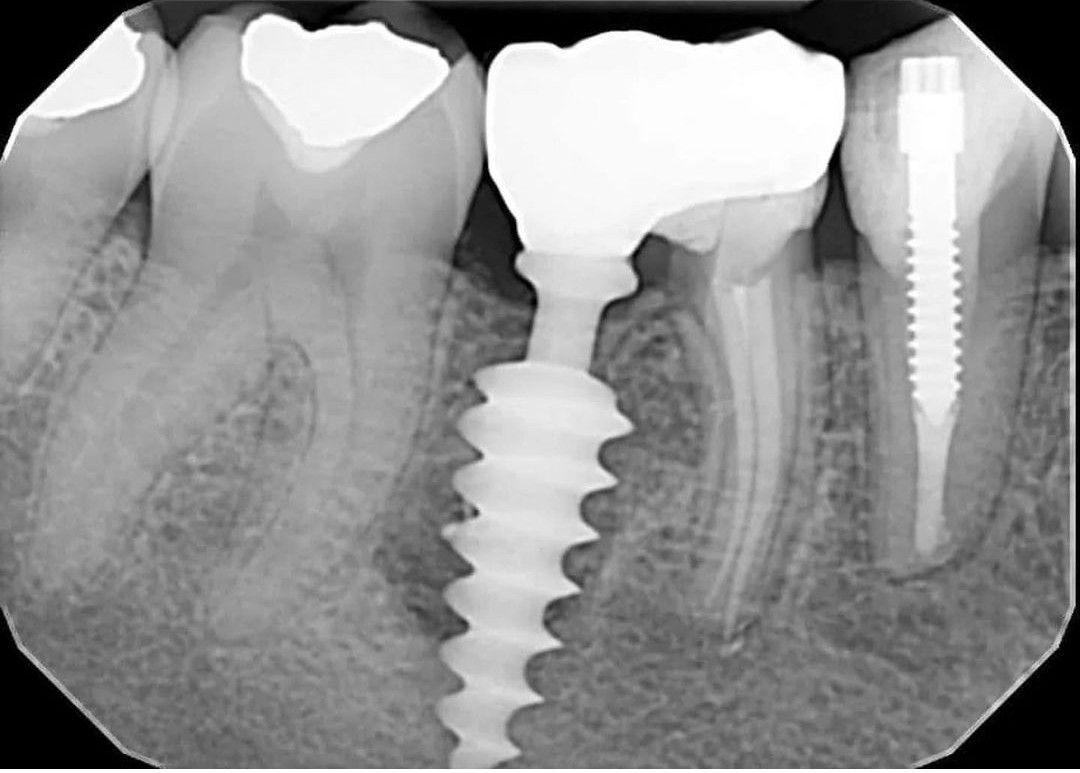

Implant Failure

Can you identify what went wrong here?